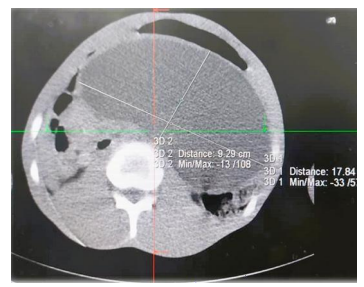

• Contrasted Enhanced CT scan: There is a large midline oval cystic mass in the lesser sac compressing and displacing the stomach supero-anteriorly measuring 21x11 cm. It has smooth thin wall and homogeneous content with no solid areas. The mass is seeing closely related to the pancreatic head, pancreatic body and tail normal appearance. Diagnosis: Pancreatic pseudocyst.

Figure 2